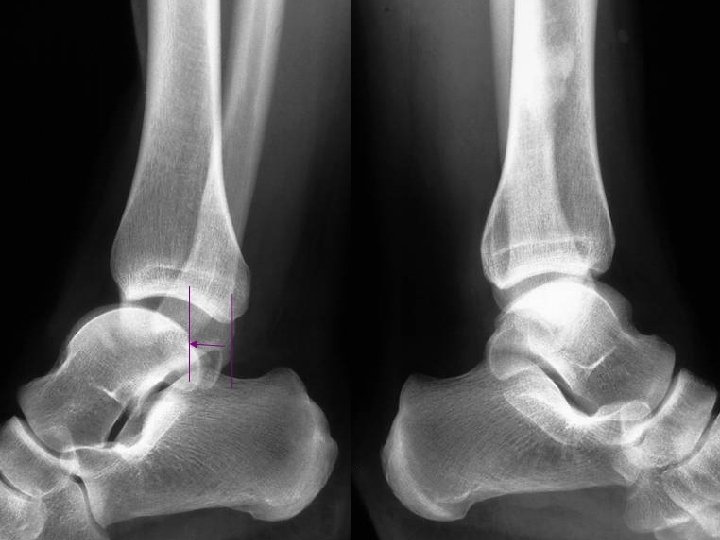

Le SCP traumatique : Mécanismes Trauma en flexion plantaire forcée n Très fréquent… n Origine : Shoot contré, tacles, irrégularité du sol, … Lésions : - contusion « postérieure » chondrales, caps. -ligamentaire - # processus post. lat. du talus (# de SHEPHERD) - # malléole tibiale postérieure - # os trigone ou de la synchondrose n Difficultés : - DD # ou os trigone… - Arguments : - # : trait net et non corticalisé - scintigraphie n

Fracture du processus postéro-latéral